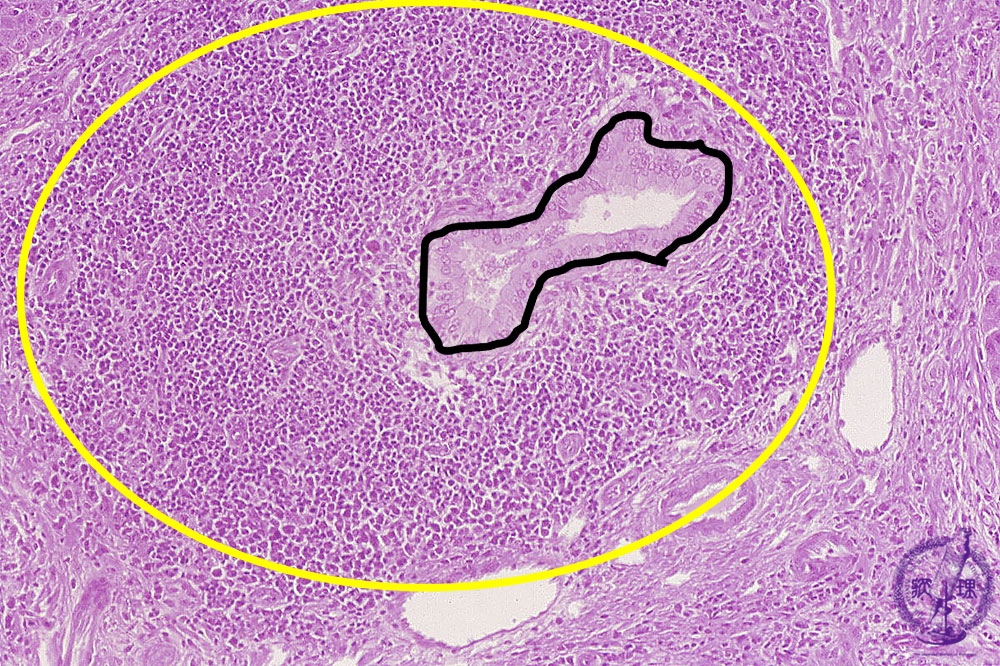

- 10.Liver

- (4)Primary biliary cirrhosis

Microscopic image (HE stain, intermediate power): There is a marked lymphocytic infiltrate (yellow circle) around bile ductules (image, center ・ black dot) within expanded portal areas and the bile ductular epithelium is damaged. These changes are characteristic of chronic non-suppurative cholangitis.

Click the image to see the enlarged image.